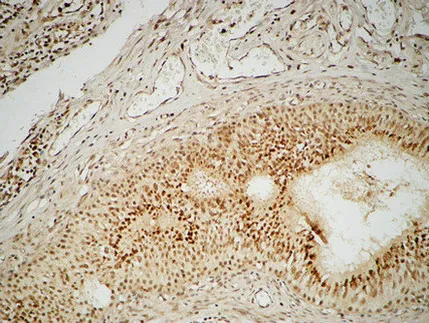

ETS1 Rabbit Polyclonal Antibody

Cat: APRab10649